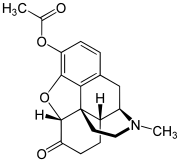

- Esters of morphine opiates: slightly chemically altered but more natural than the semi-synthetics, as most are morphine prodrugs, diacetylmorphine (morphine diacetate; heroin), nicomorphine (morphine dinicotinate), dipropanoylmorphine (morphine dipropionate), desomorphine, acetylpropionylmorphine, dibenzoylmorphine, diacetyldihydromorphine;[261][262]